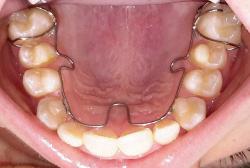

ALF ( Advanced Light Force

ALF Therapy has proven to be an extremely valuable tool for those patients who have:

• A need for facial guidance

• Palate expansion

• Narrow palates

• Breathing issues

• TMJ dysfunction

• Craniofacial pain

• Crowded/crooked teeth

• An avoidance for extractions

• Crossbite, overbite or underbite

• Cranial asymmetry

• Sleeping problems — snoring

• Recommendations for jaw surgery

Our ALF appliances are certified by Dr. Darick Nordstrom. He has personally instructed our ALF-certified technicians on the proper design and fabrication techniques to ensure that each technician is capable of creating authentic ALF appliances worthy of certification. The seal below is his stamp of approval.

Dr. Brown is highly trained in ALF (Advanced Light Force) therapy. He has over 500 hours in ALF therapy training and has lectured around the world teaching ALF techniques with Dr. Nordstrom, the creator of the ALF appliances. The ALF appliances are thin, conservative appliances that can be used on the upper and lower arches. They hide behind the teeth, are removable and are basically invisible when being worn. This innovative treatment approach is used to address neurological, orthodontic and orthopedic issues, and the benefits are vast. Each appliance is unique to the patient and designed by the doctor to achieve specific goals relating to health, beauty and function. No ALF appliance is the same, and treatment is pain-free.